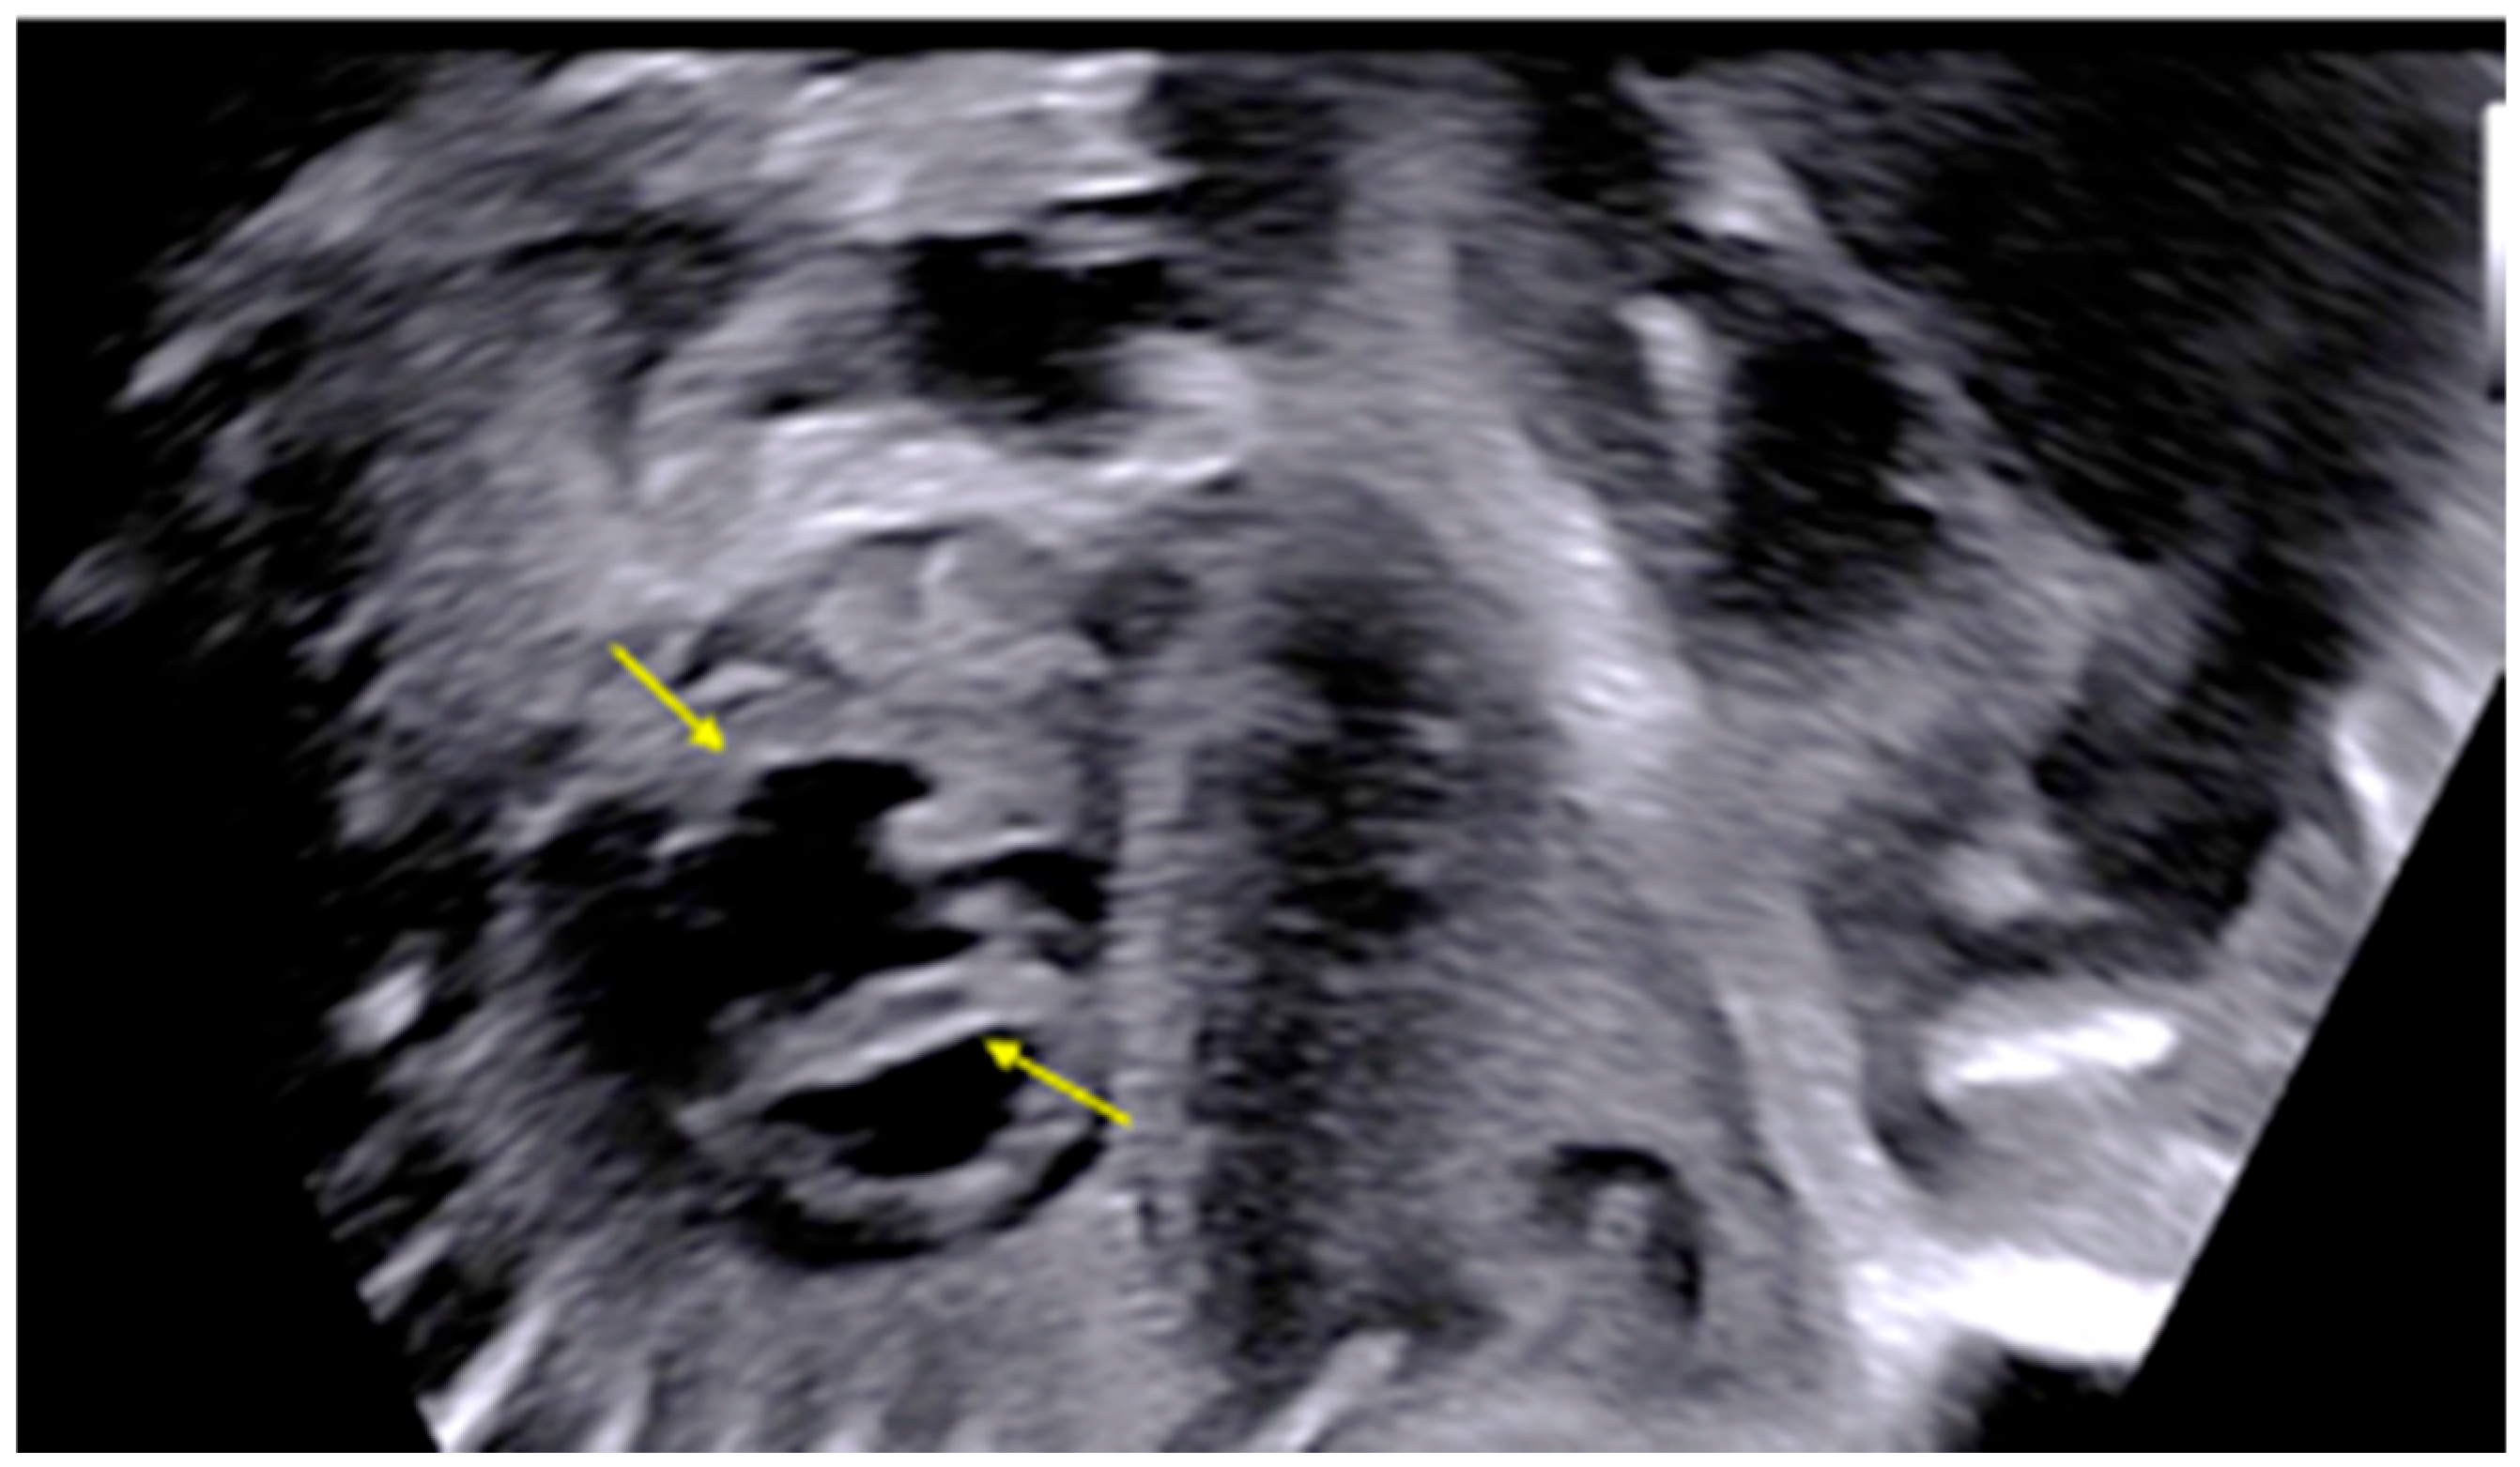

| 28 + 0 | First IVIG cycle (65 g total) | 75 | SF increased to 52%; mild improvement in contractility | Initiated due to signs of fibroelastosis |